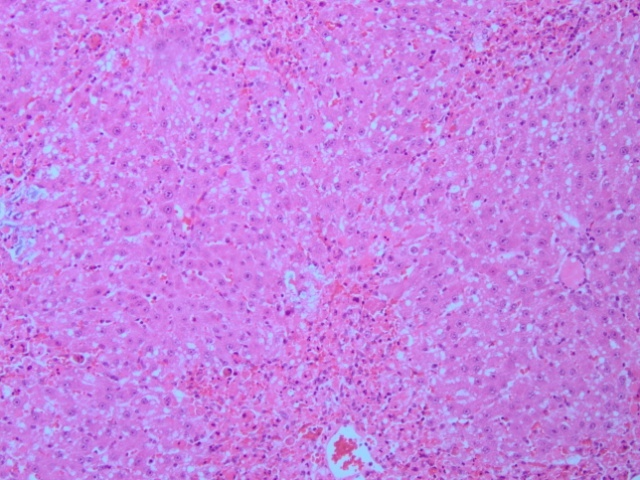

Fig. 3: Effect of M. borneensis on liver histopathological alterations in rats. (A) Saline treated control (B) CCl4 (1.2 ml/kg b. wt.) (C) MB (125 mg/kg b. wt.)+CCl4 (1.2 ml/kg b. wt.) (D) MB (250 mg/kg b. wt.)+CCl4 (1.2 ml/kg b. wt.). Specimens stained with hematoxylin and eosin (a, b, c and d) X 20)

Protective effects of M. borneensis on liver histopathology

The saline control group shows normal liver architecture as indicated in fig. 3 A. CCl4 treated group produced in focal necrosis, dense portal infiltration and inflammation (fig. 3B). Whereas rats treated with M. borneensis showed a minimum grade of necrosis and inflammation (fig. 3 C and D).

The toxicity of CCl4 has caused such extensive vascular degenerative changes and centrilobular necrosis in hepatocytes. Treatment with different doses of ethanolic extract of leaves of M. borneensis produced slightly degenerative changes and lowered the necrotic zones in the hepatocytes, indicating its hepatoprotective efficiency.